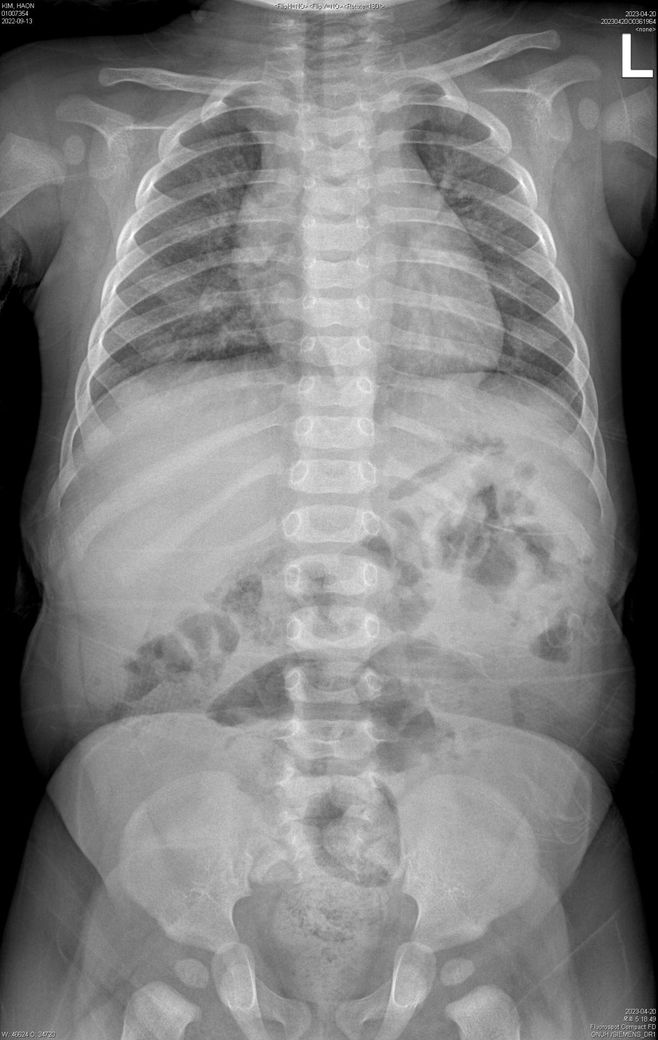

X-ray 별도 첨부 드립니다.

• 1번 째 사진

• 2번 째 사진